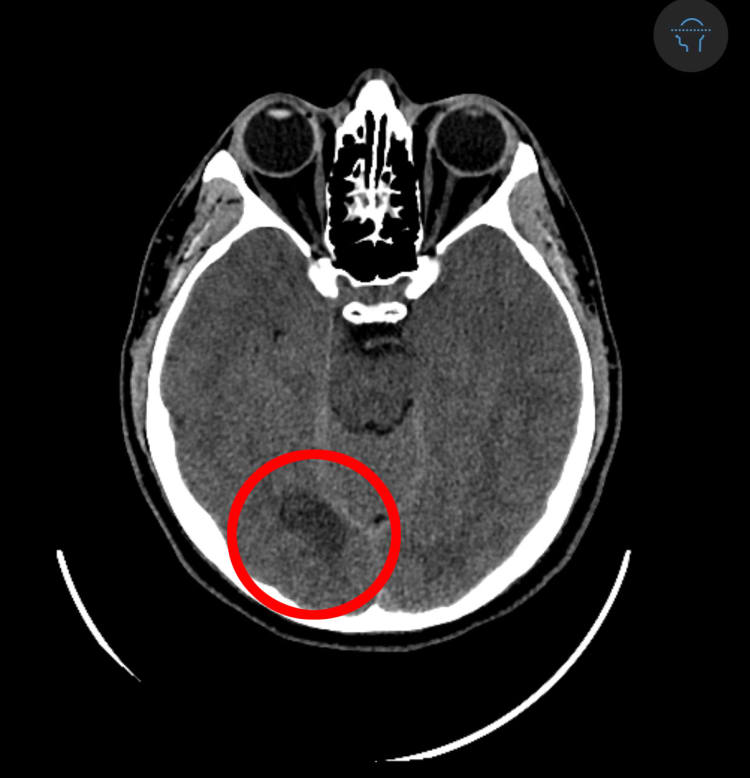

Imaging revealed a stroke in Crockett's occipital lobe.

The imaging revealed Crockett had suffered an ischemic stroke, which happens when a blood clot blocks blood flow to the brain. It occurred in his occipital lobe – the vision center in the brain – which is why he had multiple retinal migraines.

Following the MRI, the Stroke Neurology team performed a CT angiogram – an imaging test that shows blood vessels and flow – of the head and neck to make sure there were no significant blockages or other diseases that would raise his risk of another stroke.